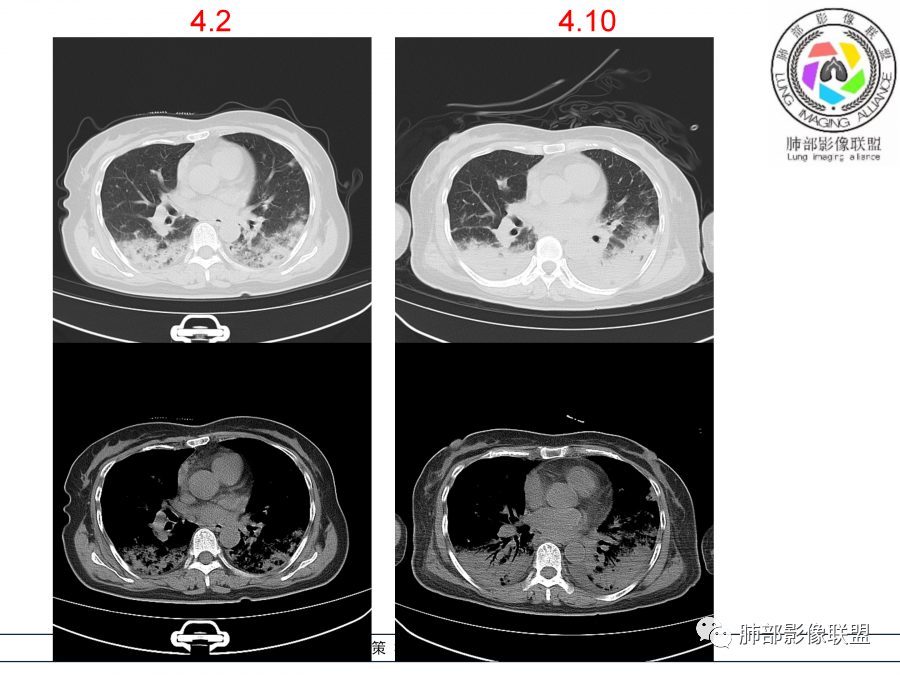

影像,第一次双肺中下叶胸膜下多发斑片状实变影,部分融合成,周围散发磨玻璃影,磨玻璃影内可见小叶间隔及小叶内间隔增厚,病变平行于胸膜,第二次间隔8天,双肺实变影明显进展,有重力作用,支气管近端堵塞,进展较快,临床有发热,血沉高,狼疮SLE阳性,考虑1:OP(机化性肺炎)2:SLE相关肺炎,建议支气管镜灌洗液病原学检测。

➢患者7天前起因受凉后出现阵发性咳嗽,无明显时间规律性,咳黄白粘痰,发热,体温最高达39.5℃,伴鼻塞、流清涕,。两肺下叶背段,后基底段为主的渗出性的病变,短时间内病变明显的增多,双侧胸腔积液,狼疮全套抗R0/SS检测阳性,考虑狼疮性肺损,机化性肺炎?鉴别结核

老年女性,咳嗽咳痰伴发热7天,白细胞不高,血沉快,降钙素原不高。其他化验未见明显异常,狼疮全套抗Ro/SSA阳性,双肺野靠近胸膜下磨玻璃实变影,支气管通畅,有充气征,沿胸膜下分布,有细网格征,7天后进展明显,实变影加重,胸膜肥厚,胸水不明显,心包少量积液?抗感染治疗无效,考虑非感染性疾病可能性大,结缔组织相关性肺病?狼疮性肺炎?机化性肺炎?鉴别病毒性肺炎。

老年女性,咳嗽咳痰发热7天。无气促。白细胞计数不高,PCT稍高,PPD(+),抗Ro/SSA阳性。CT:双肺野靠近胸膜下磨玻璃实变影,支气管通畅,有充气征,沿胸膜下分布,有细网格征。予抗生素治疗,8天后复查胸部CT见病灶范围扩大,实变影加重,胸膜肥厚,胸水不明显。抗感染治疗无效,考虑有:1.非感染性疾病:结缔组织相关性肺病,支持点:肺部CT表现为间质性炎症病变,抗RO/SSA(52)阳性;2.病毒性肺炎:患者无气促症状,可能性小;3.肺结核。

第一次双肺中下叶胸膜下多发斑片状磨玻璃及实变影,病变平行于胸膜,支气管通畅,8天后,双肺实变影明显进展范围扩大,部分支气管近端堵塞,进展较快,胸腔积液,抗感染治疗无效,考虑:非感染性疾病:结缔组织相关性肺病。鉴别机化性肺炎。